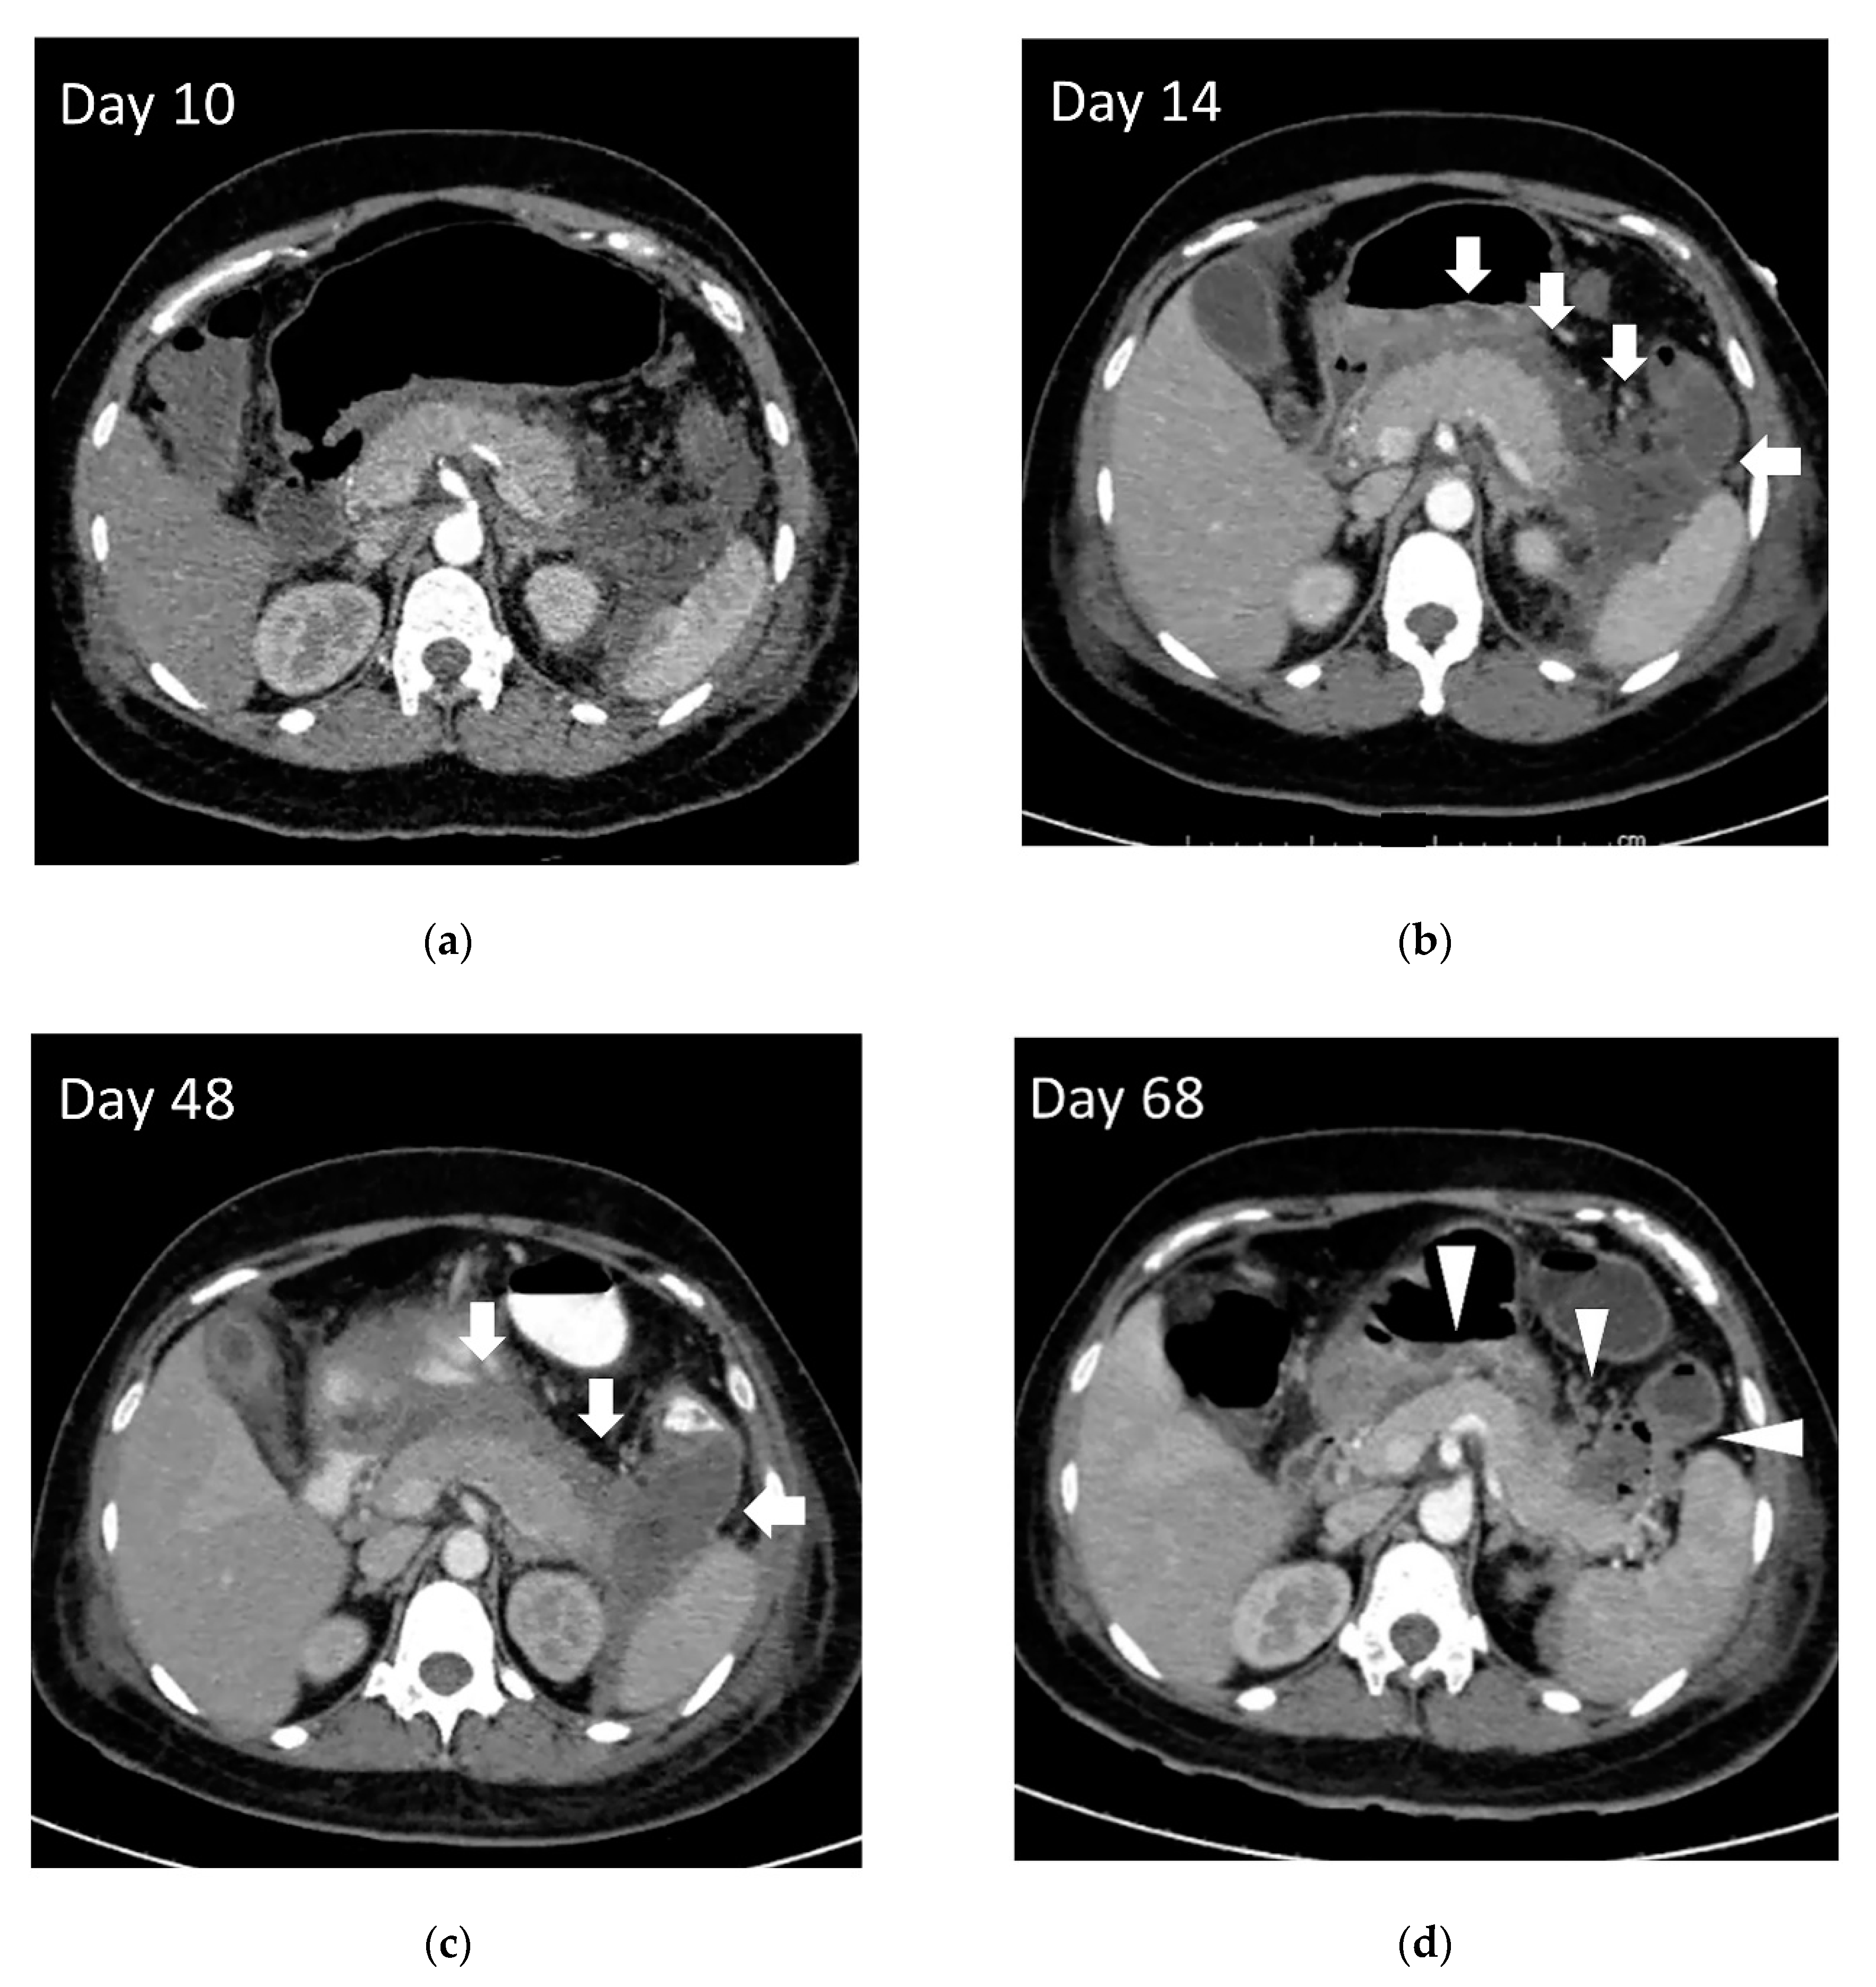

2. Evolution of Pancreatic Fluid Collection